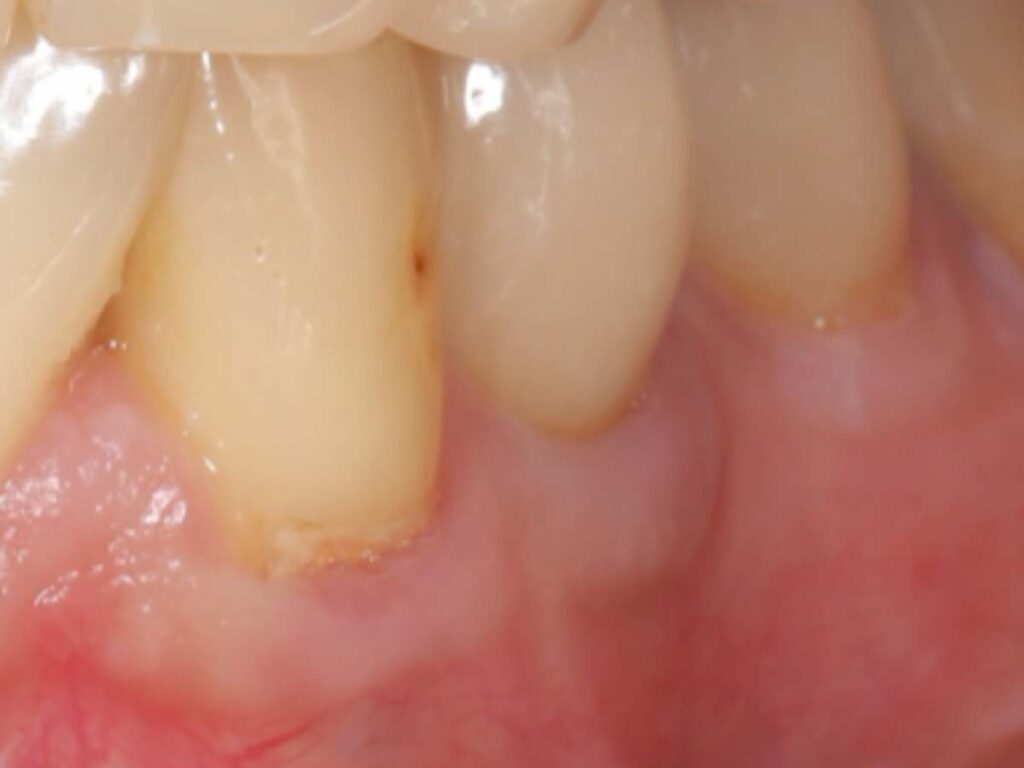

- 術後側方面観(術後10年以上経過)

- 術後正面観(術後10年以上経過)

この方法により、単に虫歯を治すだけでなく歯根の露出を改善、歯ぐきの厚みを回復、再び虫歯になりにくい環境を作るという根本的な改善を目指しました。

結果として、術後10年以上経過しても歯肉は安定しており、根元の虫歯の再発も認めていません。